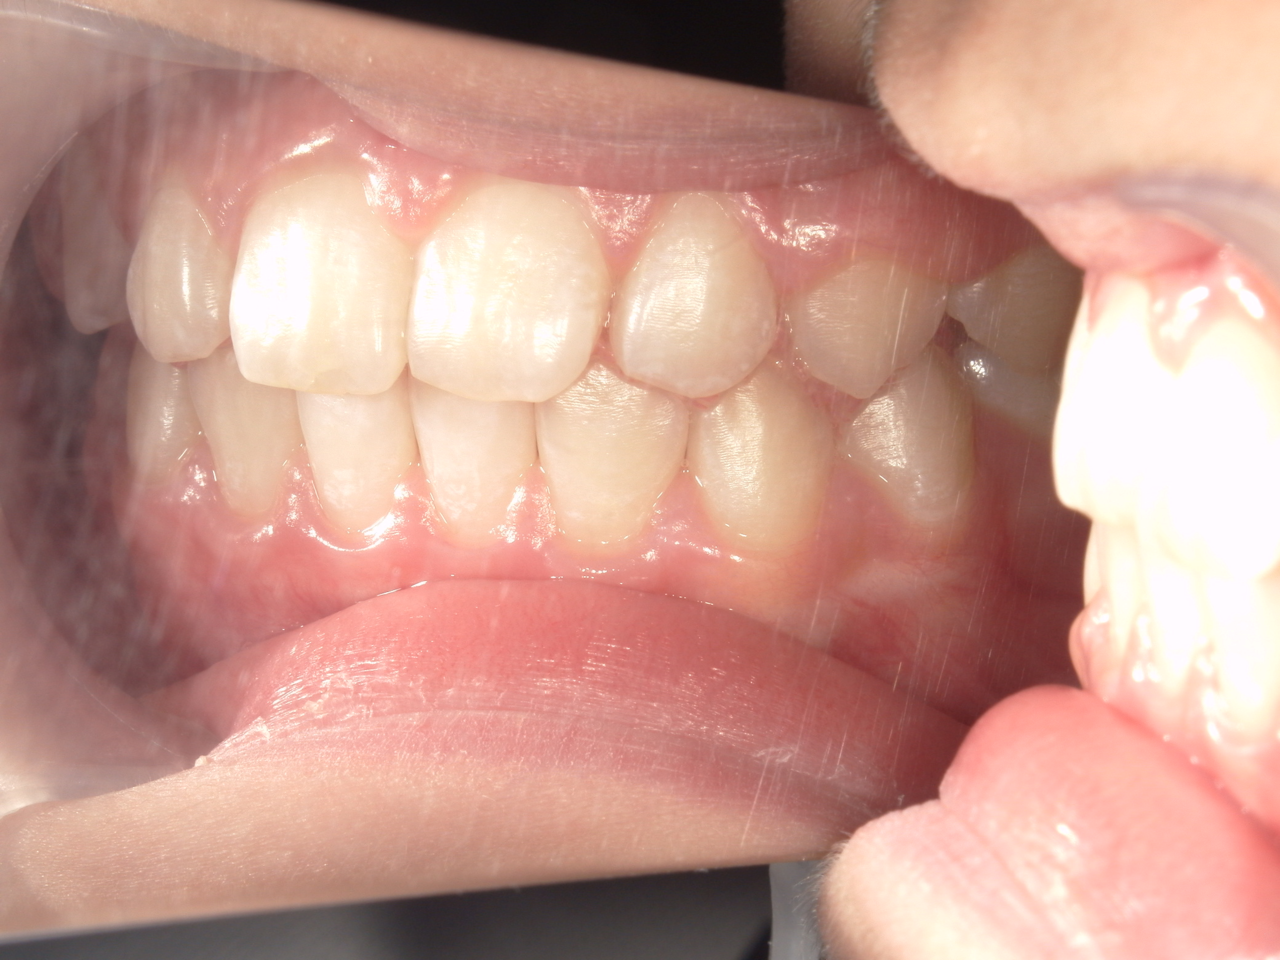

治療後

治療の副作用(リスク)歯の動き方には個人差があり、予想された治療期間が延長する可能性があります。。床矯正の使用状況、矯正歯科治療には患者さんの協力が必要であり、それらが治療結果や治療期間に影響します2次矯正が必要になる場合もあります。

治療の副作用(リスク)歯の動き方には個人差があり、予想された治療期間が延長する可能性があります。。床矯正の使用状況、矯正歯科治療には患者さんの協力が必要であり、それらが治療結果や治療期間に影響します。2次矯正が必要になる場合もあります。